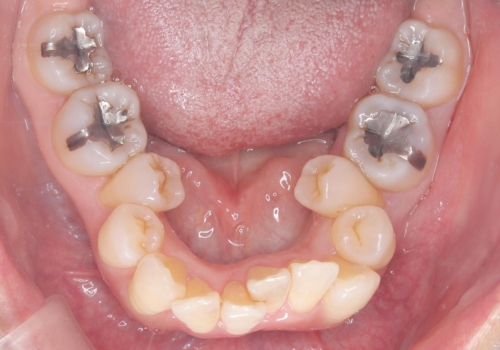

- 主訴:口を開けると所々入っている銀の詰め物が目立つので白い物にやり替えたい。

下顎大臼歯部に入っている保険適用のメタルインレーを、適合性と審美性の良いセラミックインレーでのやり替えとなりました。